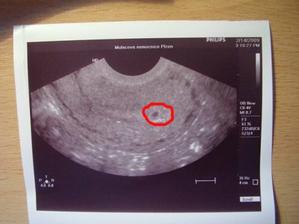

.Doktor příčinu bolesti nezjistil.Mimčo je v naprostém pořádku,juchů.Ze zprávy od dr : V dutině děložní gestační váček s echem žloutkového váčku,s naznačeným embryonálním polem,dle GSD 5+3 tt,vidím pulzaci septum primum.Takže UŽ MÁME AKCI PRIMITIVNÍHO SRDCE,tralala